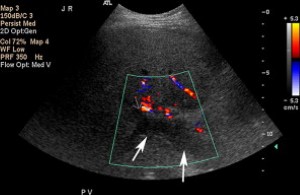

Nguyên nhân hiếm gặp của đảo ngược dòng chảy trong hệ tĩnh mạch cửa là rò động-tĩnh mạch [14]. Các dị dạng động-tĩnh mạch bẩm sinh rất hiếm và phần lớn các rò động tĩnh mạch là do can thiệp (tai biến của sinh thiết gan) hoặc chấn thương. Đôi khi rò kết hợp với tổn thương khu trú [14]. Trên siêu âm, nhánh tĩnh mạch cửa có dòng đảo chiều, trong khi đó động mạch gan có dòng chảy rối với tốc độ tâm trương tăng và RI thấp (Hình 7) [15]. Thông thường, RI của động mạch bị rò thường giảm 30% đến 40% so với động mạch ở các thùy bình thường [15].

Hình 7. Rò động-tĩnh mạch ở bệnh nhân nam 26 tuổi bị viêm gan C, trước khi siêu âm vài tháng đã sinh thiết. (Hình A) Ảnh siêu âm màu và duplex Doppler phát hiện ngành trái tĩnh mạch cửa có dòng chảy đảo chiều. Lưu ý có chảy rối và có khảm màu khu trú (mũi tên). (Hình B) Động mạch gan trái có dòng chảy rối, tốc độ tâm trương tăng so với động mạch gan chính. Cũng lưu ý ổ khảm màu. (Hình C) Ảnh duplex Doppler và màu của thân tĩnh mạch cửa và động mạch gan cho thấy dòng chảy đẩo chiều ở tĩnh mạch và dòng chảy bình thường ở động mạch.